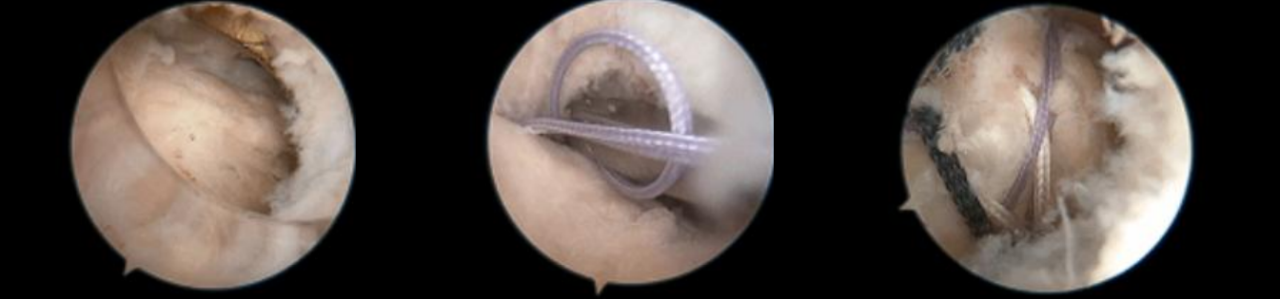

镜下双袢联合高强线“三重固定”

步骤1:暴露骨折段,插入定位器械,并构建一个直径为4.0mm的骨隧道。

步骤2:插入两条PDS线并引入高强线,分别并将其穿过后交叉韧带,以形成初始的吊带环。

第三步:双套环高强线复位骨折块,并穿入固定微孔钛板。

步骤4:将一根高强度缝合线穿过骨隧道,并牢牢收紧,以准确复位骨折段。

第五步:拉紧双环以稳定骨折部位,并抓住两条牵引缝线。

步骤6:紧固牵引缝线以防止固定环滑脱。